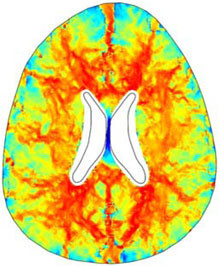

A numerical finite element model of one human brain is built in COMSOL in order to study a particular form of hydrocephalus, the so called Normal Pressure Hydrocephalus (NPH). The geometry of the ventricles and the skull is obtained by Magnetic Resonance Imaging (MRI) and imported in COMSOL Multiphysics. Form the mechanical point of view, the brain parenchyma is modeled as a porous medium fully saturated with the Cerebro-Spinal Fluid (CSF) using the Biot’s theory of consolidation. Diffusion Tensor Imaging (DTI) is used to establish locally the direction of the bundles of neurons (fiber tracts). Novel ideas are introduced to link the diffusion with CSF permeability in brain. To find out the influence of the anisotropy in permeability, two models are tested under the same CSF pressure gradient.